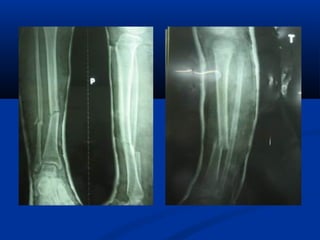

- 1.

- 3.

I. Chæ ñònh:

-Caétboät söûa truïc ñöôïc aùp duïng trong caùc tröôøng

hôïp maø sau khi naén xöông baêng boät xöông coøn bò

gaäp goùc nhieàu hôn 15 ñoä

- Boät phaûi khoâ cöùng vaø khoâng bò loûng boät